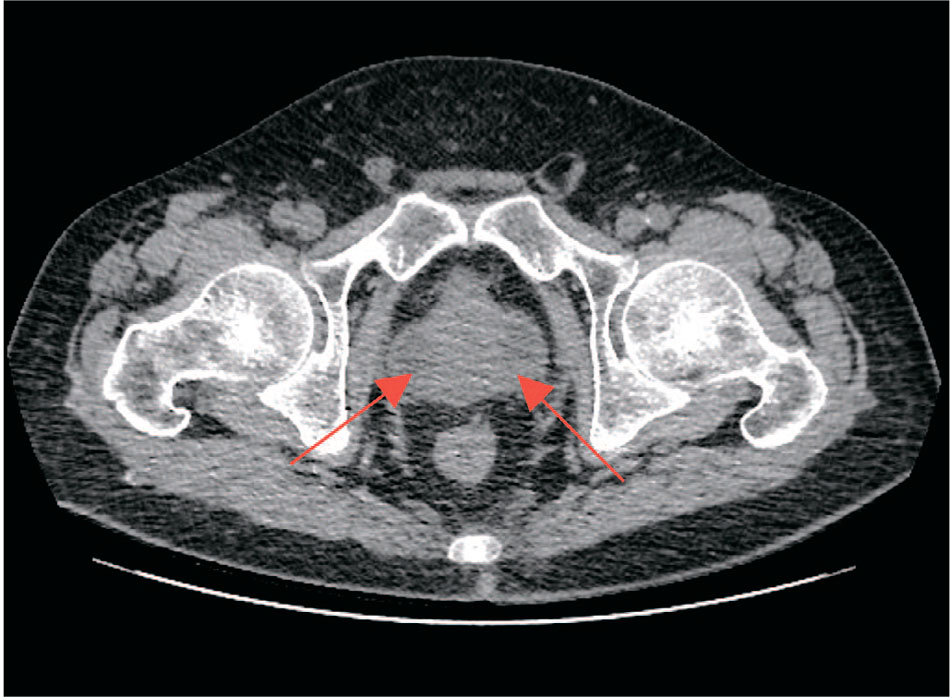

10 декабря 2024 г. пациент вновь был доставлен в стационар с жалобами на ухудшение состояния и повышение температуры тела до 38,5°C. Нативная компьютерная томография (КТ) почек и мочевыводящих путей выявила увеличение предстательной железы до 50 см3 с наличием в периферических отделах зон пониженной плотности (28×21 мм, плотностью около 9 HU), что вызывало подозрение на АПС (рис. 1). Трансректальное ультразвуковое исследование (ТРУЗИ) подтвердило увеличение объема предстательной железы до 71 см3 с неоднородной эхоструктурой. В боковых долях визуализировались жидкостные образования: в левой доле – 33×26 мм, правой – 38×31 мм. Образования имели четкие контуры, плотную капсулу и отсутствующий кровоток.

Рис. 1. Нативная компьютерная томография почек и мочевыводящих путей (стрелки указывают на абсцессы в переферической зоне предстательной железы)

Fig.1. Non-contrast computed tomography of the abdomen and pelvis (arrows piont to abscesses in the peripheral zone of the prostate gland)